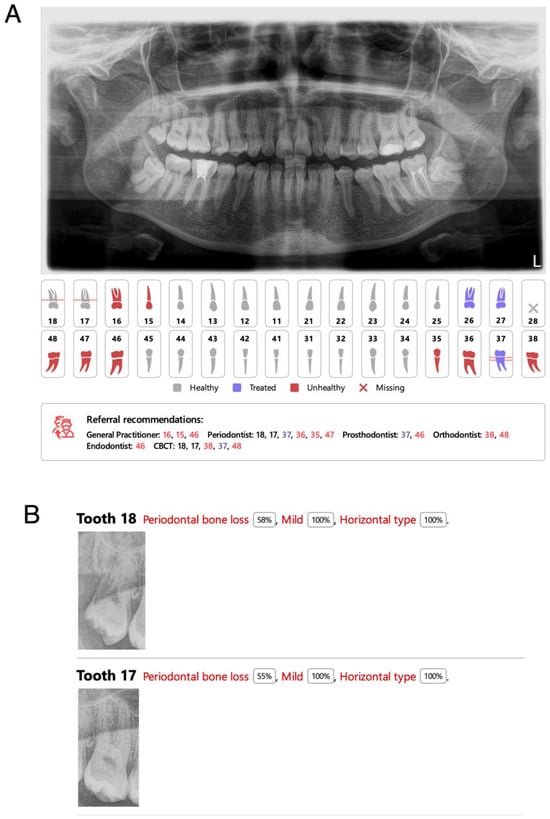

3.8. Periodontal Bone Loss